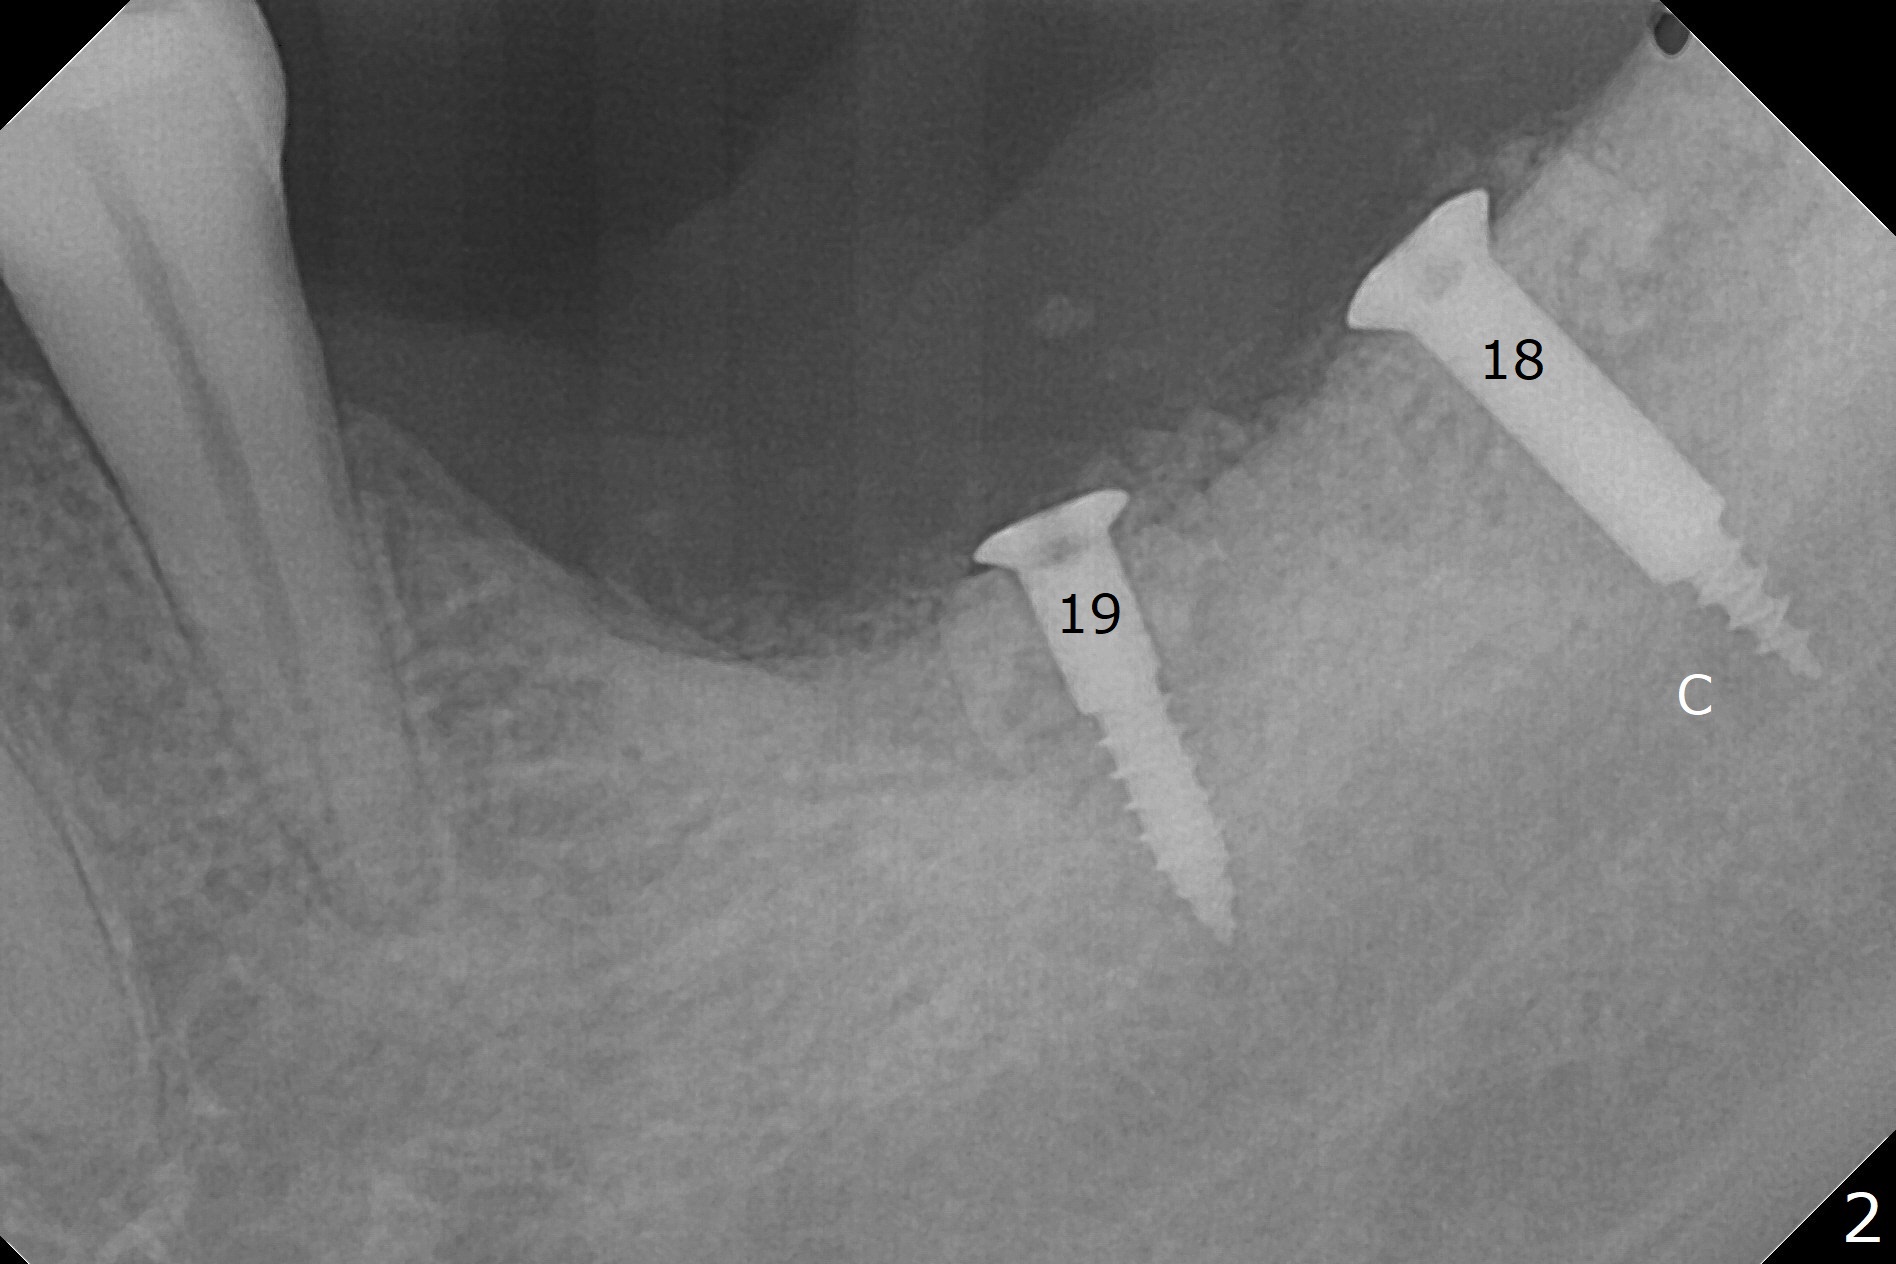

While the implant at #18 is easily removed, the one at #19 is superficial with buccal nonkeratinized gingiva (Fig.1). The latter is removed. Two small pieces of onlay graft is harvested from the left ramus and fixed in the defects with pins (Fig.2), surrounded by allograft with PRF. Since the pin at #18 looks violating the Inferior Alveolar Canal (Fig.2 C), CT is taken. In fact the pin perforates the lingual plate at #18 (Fig.4, as compared to Fig.3 (#19)). It leaves in place. Postop the wound dehisces with loss of allograft and exposure of the screws. The wound heals gradually mesiodistal with exposure of #18 screw 2.5 months postop. Follow up is disrupted by coronavirus pandemic.

It appears that short implants could be placed mesial to the original sites (Fig.5,6), 5x6 and 5x5 mm at #19 and 18, respectively, with guide as lingual as possible. The exposed buccal threads will be covered by 3-D Bond (Fig.9 white line, post decortication (red)), collagen plug and PGA suture. Healing screws are most likely used, although healing abutments should be prepared if they help wound closure.